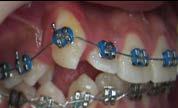

Tratamiento de caninos retenidos superiores en paciente en crecimiento con clase II división 2. Reporte de caso clínico

Los caninos retenidos constituyen una alteración eruptiva frecuente, con mayor prevalencia en la arcada superior. Su etiología es multifactorial y puede interferir con el trayecto normal de erupción, comprometiendo la oclusión y la estética.

Objetivo: Corregir una maloclusión Clase II división 2 mediante tratamiento ortodóntico en un paciente en crecimiento con ambos caninos superiores retenidos. Metodología: Se presenta el caso de un paciente masculino de 12 años, en dentición permanente, con perfil convexo, patrón dolicofacial y Clase II esquelética. Se realizó tratamiento ortodóntico sin extracciones. Para la tracción y alineación de los caninos retenidos se emplearon resortes abiertos (open coil springs) para la creación de espacio. Resultados: